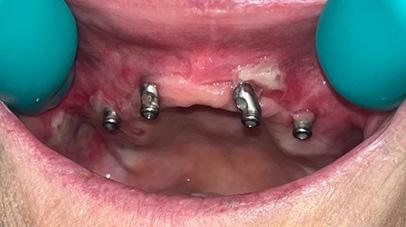

A 76-year-old post-menopausal female presented to the University of Oklahoma Advanced Education in General Dentistry, AEGD, Program in April of 2023. She was seeking comprehensive care to address her failing dentition. After discussion with previous AEGD and Oral Surgery residents, the patient decided to proceed with a full mouth extractions, ostectomy, implant placement, and a Conus overdenture on both the upper and lower arches.

In June of 2023, the patient reported to the AEGD clinic for full-mouth extractions, ostectomy, and implant placement on both upper and lower arches. Following this, an immediate upper and lower denture were delivered for her convenience.

After three months of healing, the patient returned to the AEGD clinic to confirm osseointegration of implants and to begin the overdenture fabrication process. At the final impression appointment, signs of arthritis including knuckle enlargement were noted. Due to this finding, it was determined that changing the patient's final prosthesis from a Conus overdenture to a conventional overdenture was in the best interest of the patient, as the Conus would be too cumbersome for her. As seen in Figures 1 and 2, the outcome turned out very well and the patient was pleased with results and esthetics.

FIGURE 3

FIGURE 4